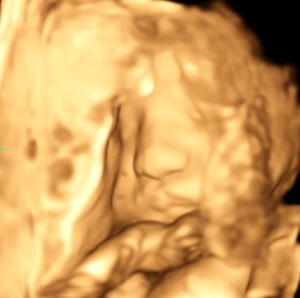

다일아 건강하게 자라서 2차기형아 검사때 만나자.

닉네임_이*정_101

2025-04-05

7

3